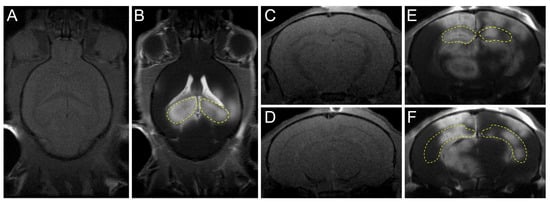

| Kong (2022) [42] | 5×FAD mice | CF:0.5 MHz PRF:1 Hz TD:120 s AP:0.25 MPa | Hippocampi | Combined therapy of FUS and Aducanumab decreases amyloid deposits, increases neurogenesis, and attenuates cognitive function deficits. |